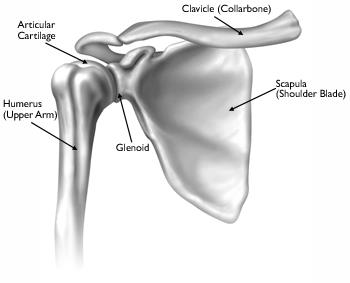

Anatomy

Your shoulder is made up of three bones: your upper arm bone (humerus), your shoulder blade (scapula), and your collarbone (clavicle). The shoulder is a ball-and-socket joint: The ball, or head, of your upper arm bone fits into a shallow socket in your shoulder blade. This socket is called the glenoid.

The bones of a healthy shoulder joint.

The surfaces of the bones where they touch are covered with articular cartilage, a smooth substance that protects the bones and enables them to move easily. A thin, smooth tissue called synovial membrane covers all remaining surfaces inside the shoulder joint. In a healthy shoulder, this membrane makes a small amount of fluid that lubricates the cartilage and eliminates almost any friction in your shoulder.

The muscles and tendons that surround the shoulder provide stability and support.

All of these structures allow the shoulder to rotate through a greater range of motion than any other joint in the body.